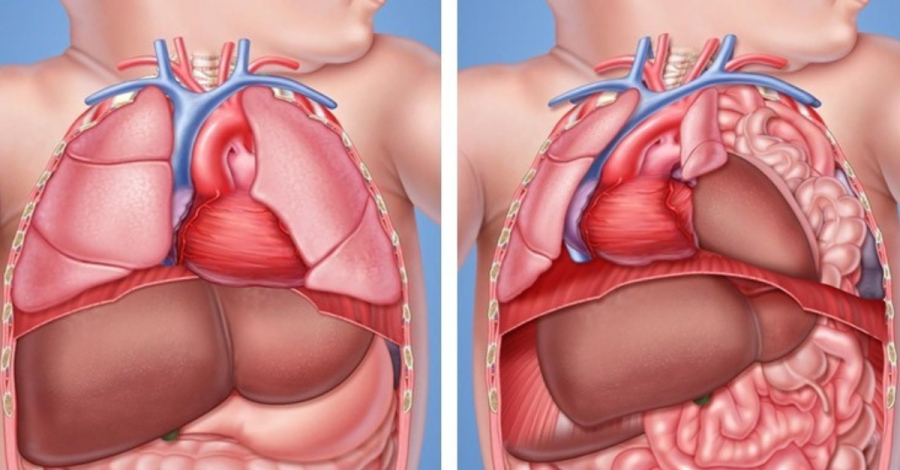

Hernias diafragmática

Hiata

• Hernias diafragmática

• Hiata